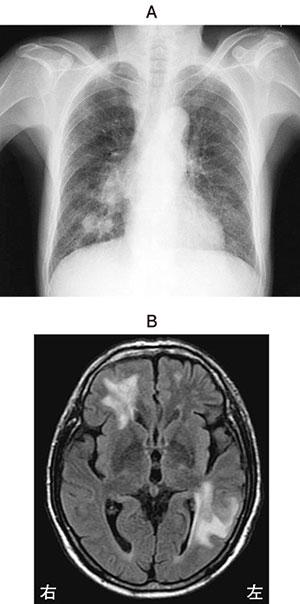

科目:

69歳の男性。肺癌。これまで化学療法を行ったが病状は進行し、経過中に脳転移がみられた。胸部エックス線写真(A)と頭部造影MRI(B)とを示す。現在、呼吸に関する自覚症状はないが、全身倦怠感、食欲不振および悪心があり、外出する気分になれず自宅に閉じこもる傾向にある。この時期に適切な理学療法はどれか。

pt3_5lAZtyEKQ_ewgvbzS

1

嚥下練習

2

下肢促通運動

3

屋外での歩行運動

4

軽打法による排痰

5

漸増的な持久性運動